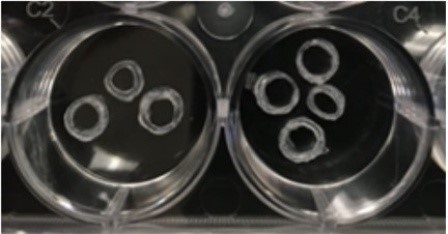

Researchers found that scaffolds loaded with strontium at any concentration stimulated wound healing A team of University at Buffalo researchers has developed a new strontium-loaded scaffold that can be personalized to fit any size dental implant and could help improve healing and tissue attachment in patients. The success of dental implants is dependent on the … Read more